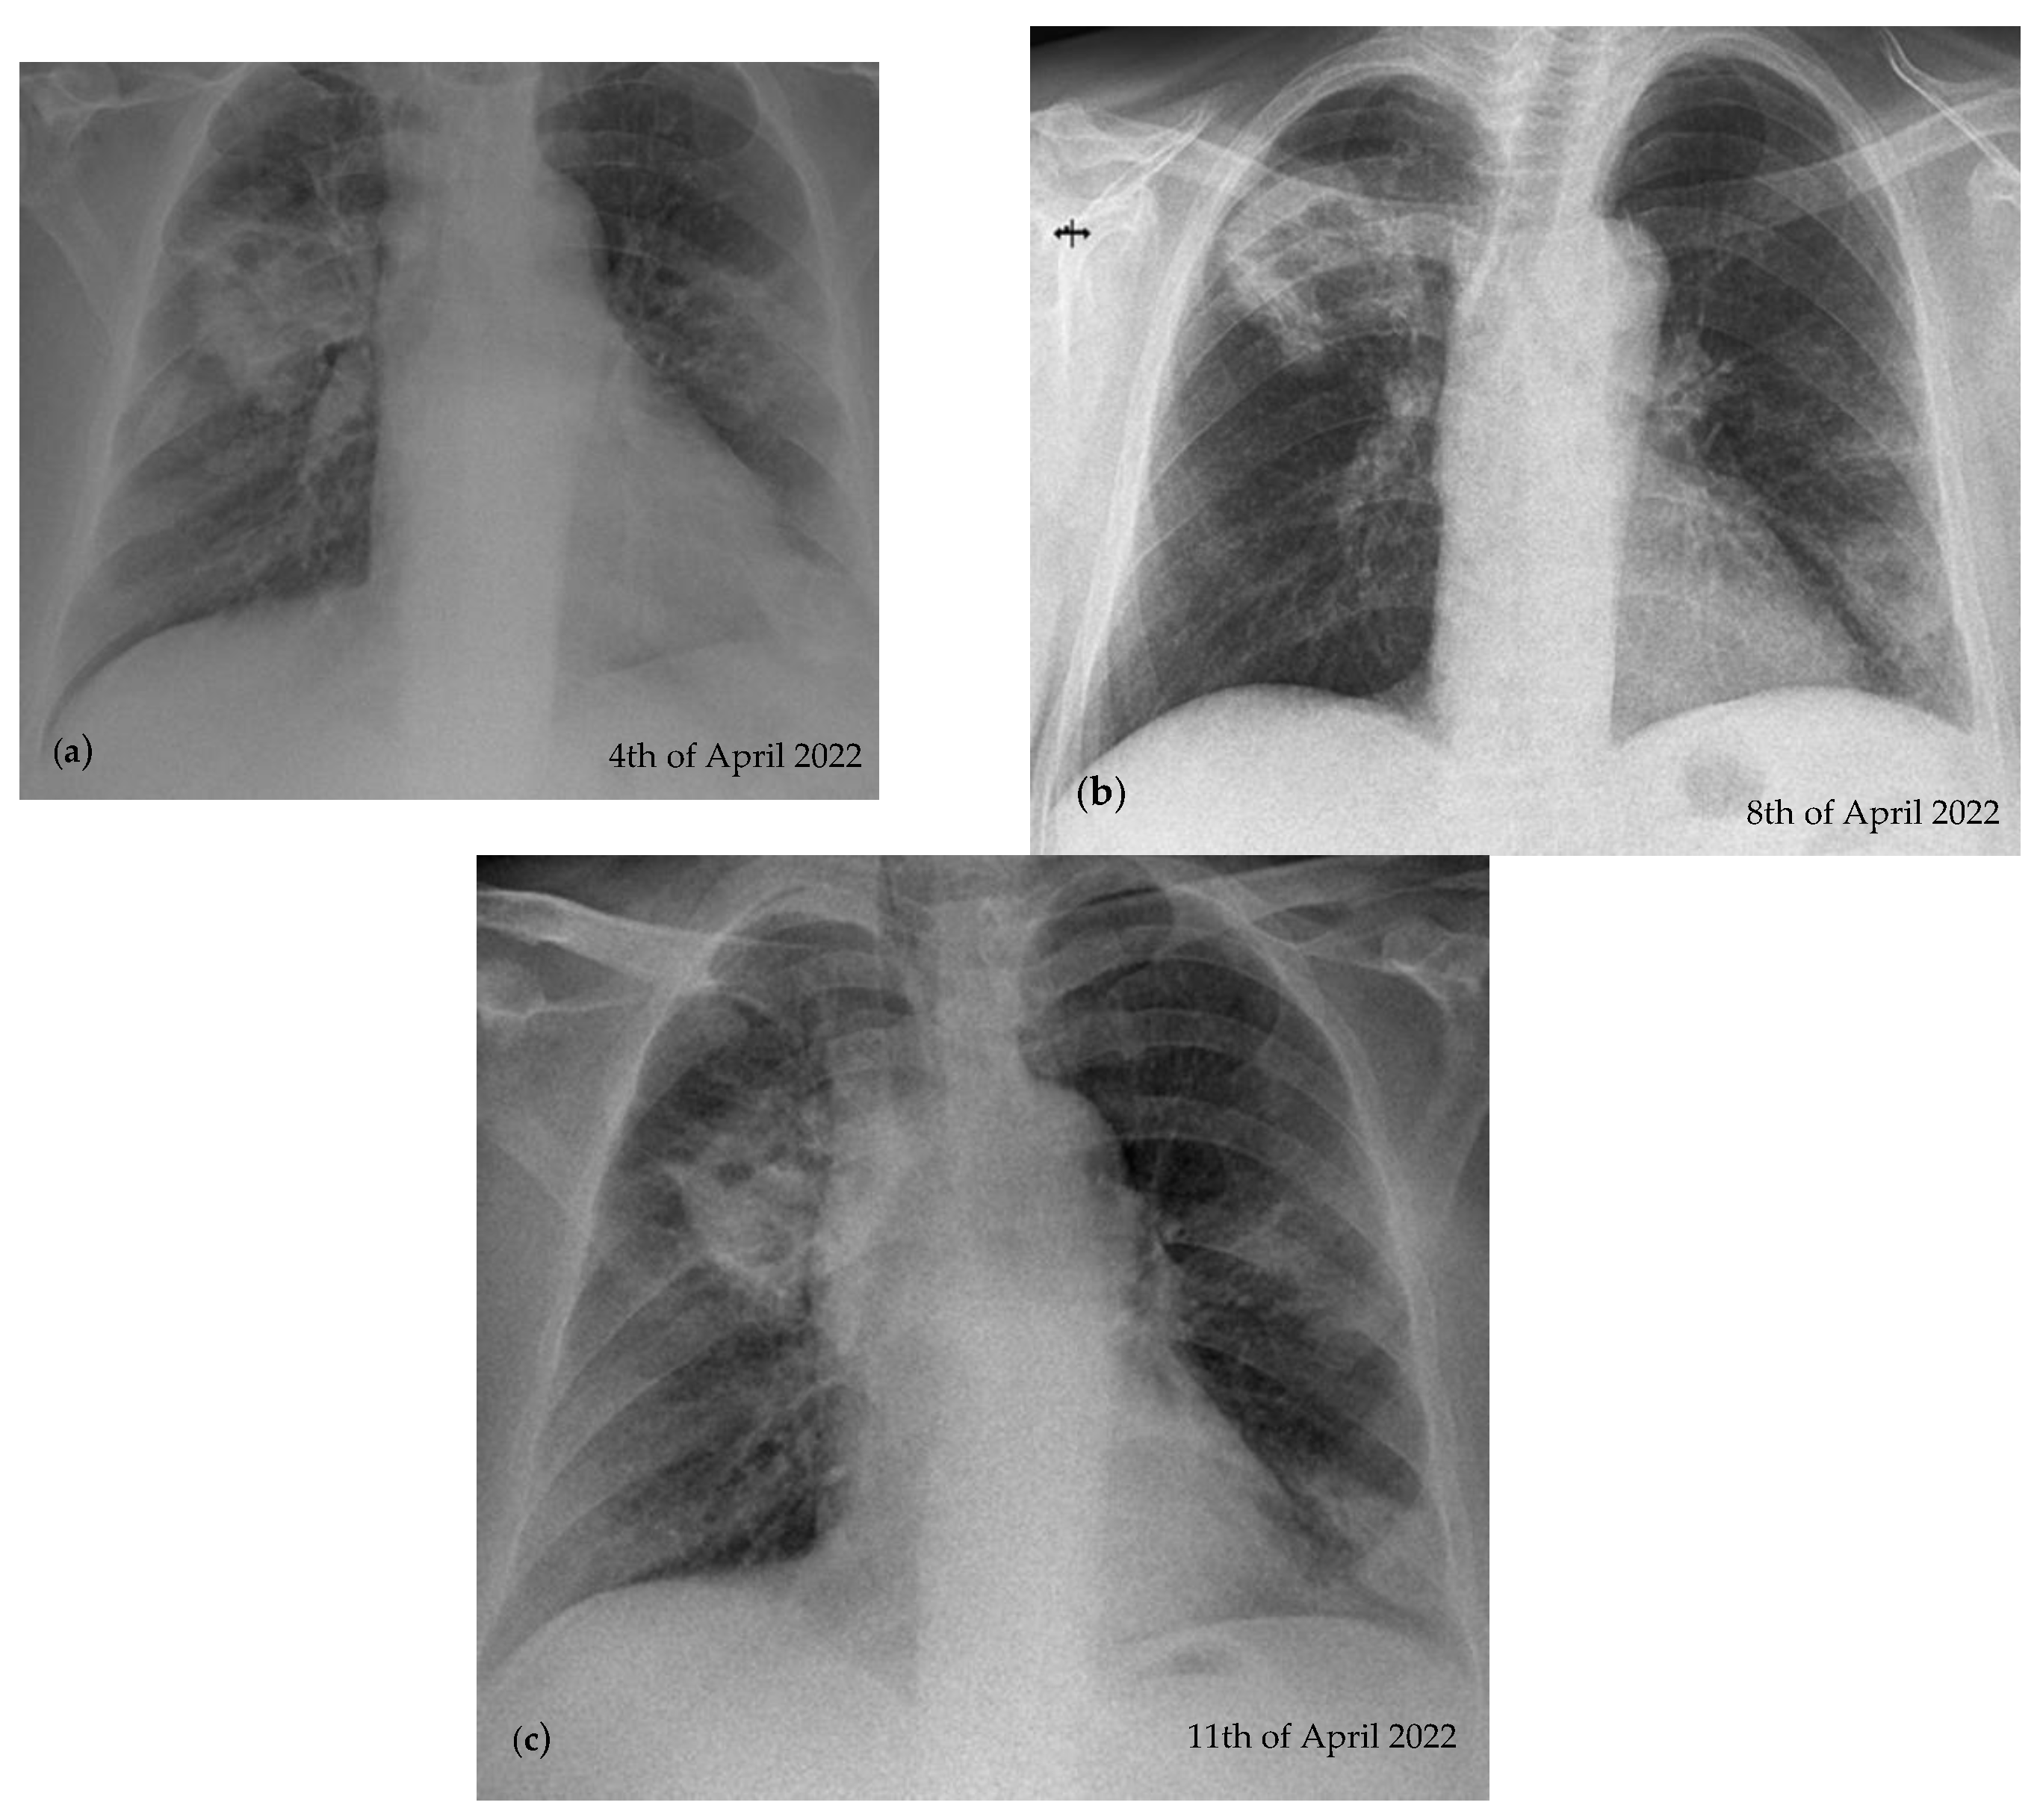

2.2. Blood Workup, Functional Tests, Bronchoscopy, and Radiological Findings

2.3. Treatment and Monitoring